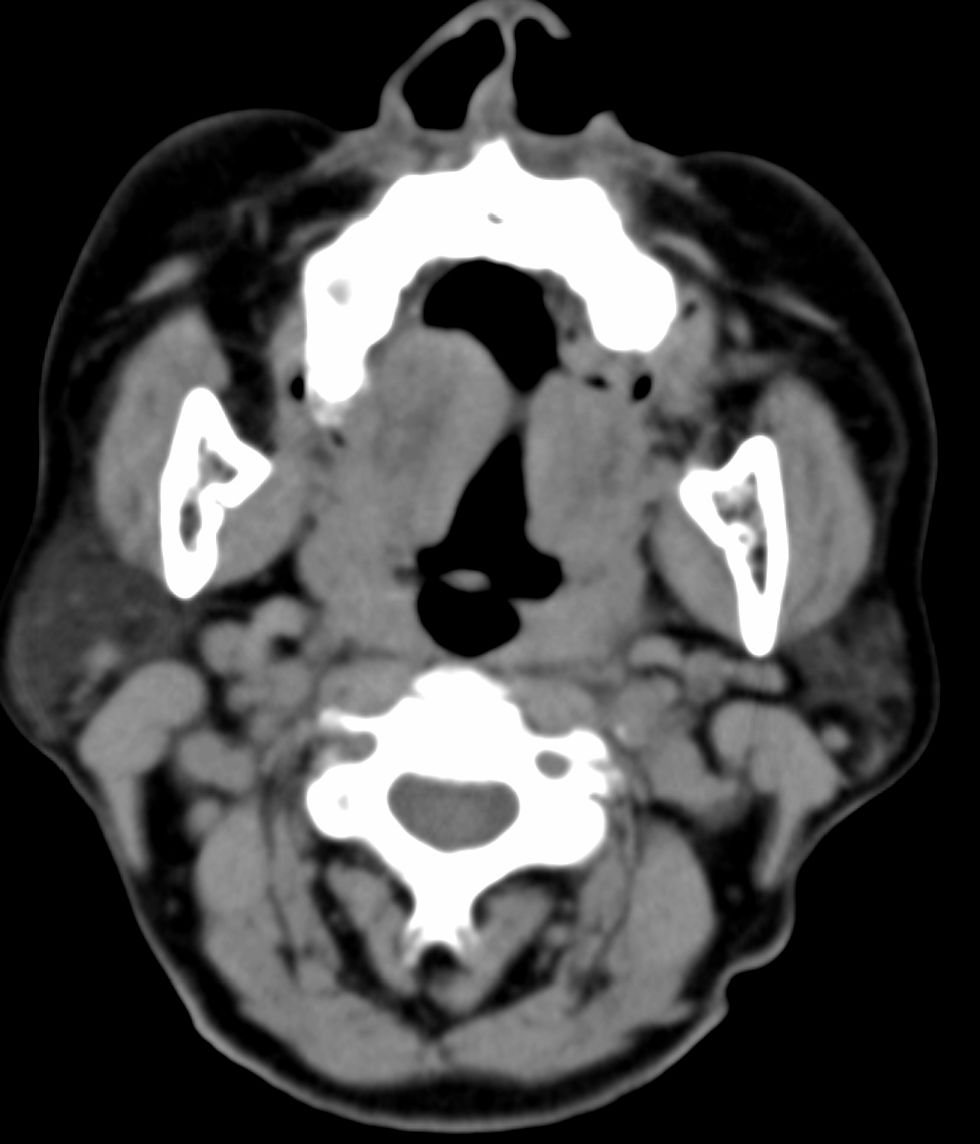

女,69岁。鼻出血2月多。(会诊病史就这样简单)鼻副窦ct检查如下:

左侧鼻腔及上颌窦见软组织块影,左侧上颌窦腔扩大,骨质吸收,右侧上颌窦见半圆形软组织密度影,鼻中隔向右侧弯曲,左侧鼻和鼻窦内翻型乳头状瘤可能性大,建议增强。

左侧上颌窦及鼻腔内见软组织密度影,其内密度不均匀,见斑片状高密度影,右侧上颌窦腔明显扩大,窦壁吸收变薄,鼻中隔右偏,右侧上颌窦见一半圆形软组织密度影,边界清楚,其内密度均匀。诊断,1、左侧鼻腔及上颌窦内翻乳头状瘤可能性大,上颌窦癌,息肉及霉菌性上颌窦炎待除外。2、右侧上颌窦粘膜下囊肿。

1)考虑左侧上颌窦内翻乳突状瘤突入左侧鼻腔。2)副鼻窦炎,右侧上颌窦黏膜下囊肿。

病理:霉菌性左侧上颌窦炎伴左侧上颌窦纤维组织增生。

窦腔密度不均匀增高,无明显钙化征象,后外侧及内侧窦壁膨胀明显,局部破坏消失,筛窦受累及,但双侧对比发现左侧窦壁骨质有硬化增白现象,这可能是支持左侧霉菌性上颌窦炎的主要依据点。